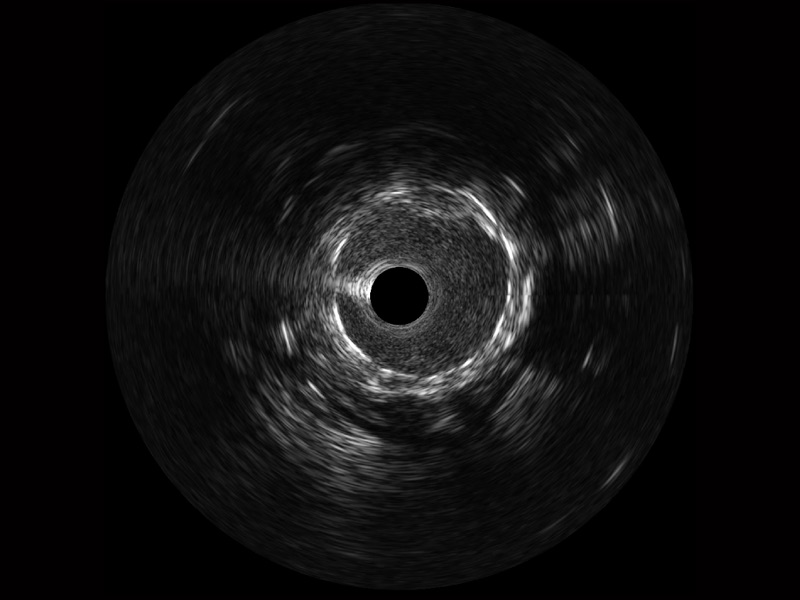

传统IVUS图像

对比传统IVUS导管成像,db真人体育官网宽频IVUS图像的近场支架梁显影更细腻,远场中膜外血管仍清晰可辨,兼顾远中近,兼顾分辨力与穿透深度